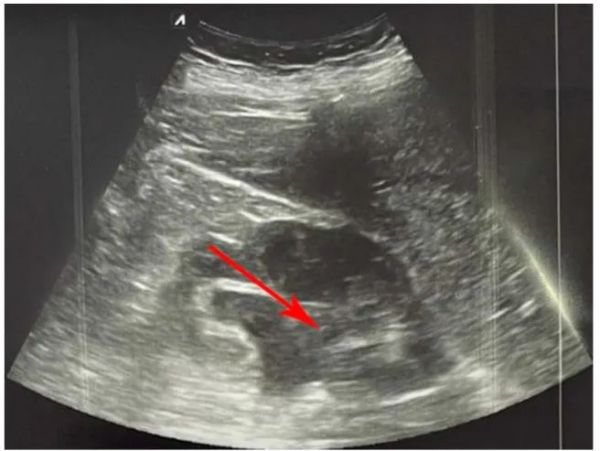

尿石症常可导致肾盂积水,肾盂积水是急性肾损伤的常见但可逆性病因[65]。与直径小于5mm的结石相比,直径大于5 mm的结石患者更常发生肾盂积水[66,67]。此外,当发生双侧肾盂积水时,也可能由于输尿管内部阻塞(例如输尿管中的肿块)或腹主动脉瘤对输尿管的外部压迫、晚期妊娠或盆腔肿块,也可能由于远端梗阻(例如前列腺肥大)而发生,因此对双侧肾脏进行美国检查非常重要[68]].通过POCUS检查,可以高灵敏度和特异性检测肾盂积水,此外还可以检测肾盂积水的程度(图 4)可以确定[65]。根据患者的体质和医生的经验,POCUS的敏感性为72%-97%,而特异性为73%-98%[64,69]。有趣的是,一项研究发现,与传统超声检查相比,由接受过5小时培训的内科医生使用POCUS检测肾盂积水的敏感性和特异性大于90%[70]。

图 4严重肾盂积水(左肾)(红色箭头)。